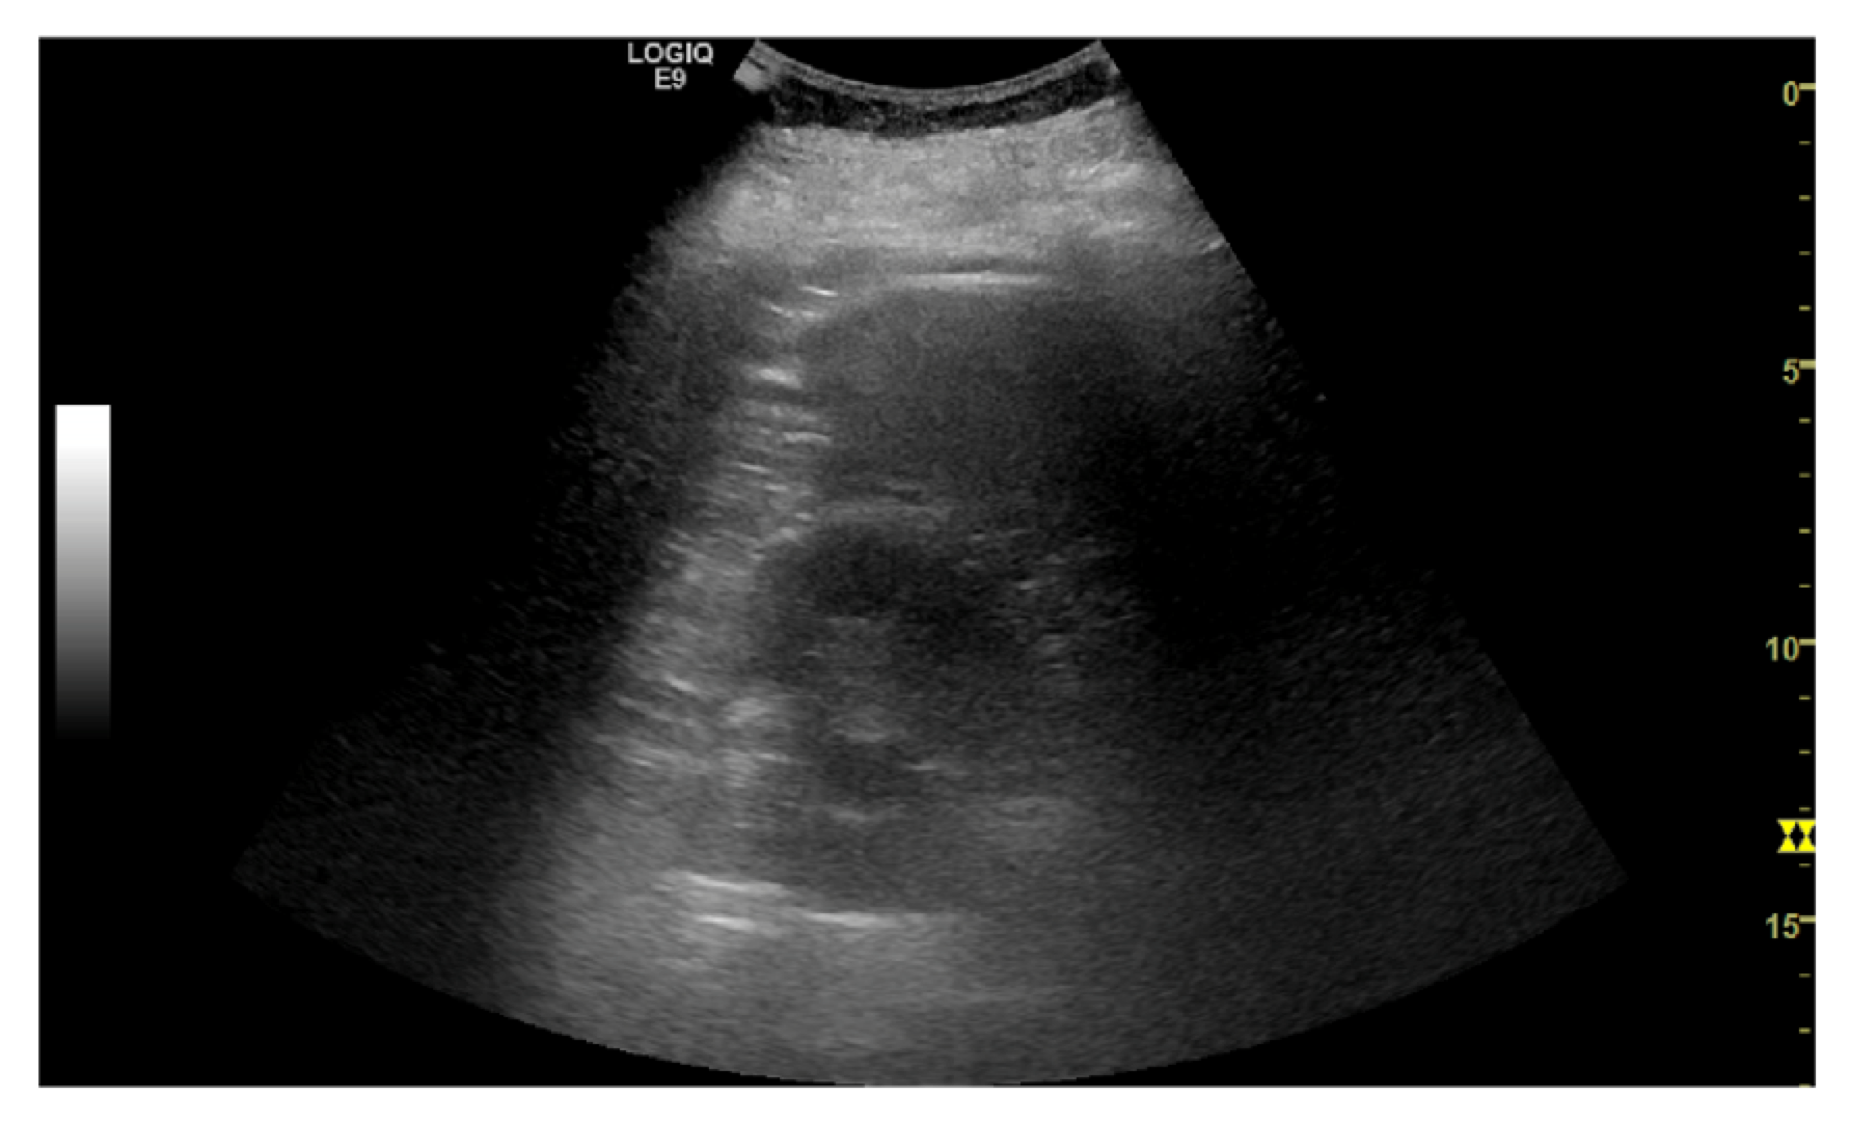

The task is to identify an optimal view for Morrison’s pouch - an anatomic site between the right lobe of the liver and the right kidney. Clinically, the view is important to identify ascites and hemoperitoneum when abnormal fluid accumulation is presented; also, it is the reference view to estimate the severity of steatosis using the hepatorenal index. Therefore, quantifying the view quality is crucial in an ultrasound examination. The images were reviewed by a board-certified radiologist and gave five different rankings as the quality measurement (Figure 4). Class 0 indicates the view does not include the liver or the kidney, and should not be used; while class 4 represent an optimal Morrison’s pouch view that will be used by an experienced operator. We used the ordinal encoding for the labels. (class 0: [0,0,0,0], class 1: [1,0,0,0], class 2: [1,1,0,0], class 3: [1,1,1,0], class 4: [1,1,1,1])

Refer to caption

(c) class 2

(d) class 3

Figure 4: Example of quality score